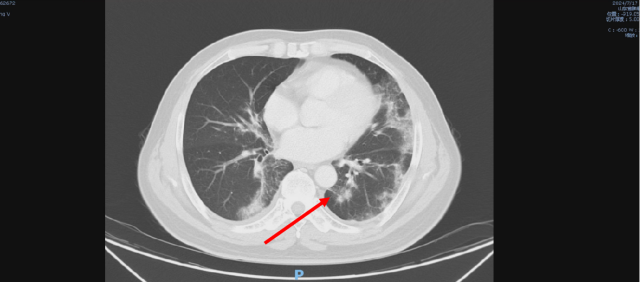

舒尼替尼治疗后,2024-04-17 复查CT

1. 结合临床,左肾癌术后;肝转移,较前(2023-05-09)进展;双肺转移,较前新发。

2. 右肺下叶少许炎症,较前变化不著。

3. 前列腺钙化灶;盆腔少量积液。

4. L5 双侧椎弓崩解;L2 椎体致密灶,变化不著,观察。